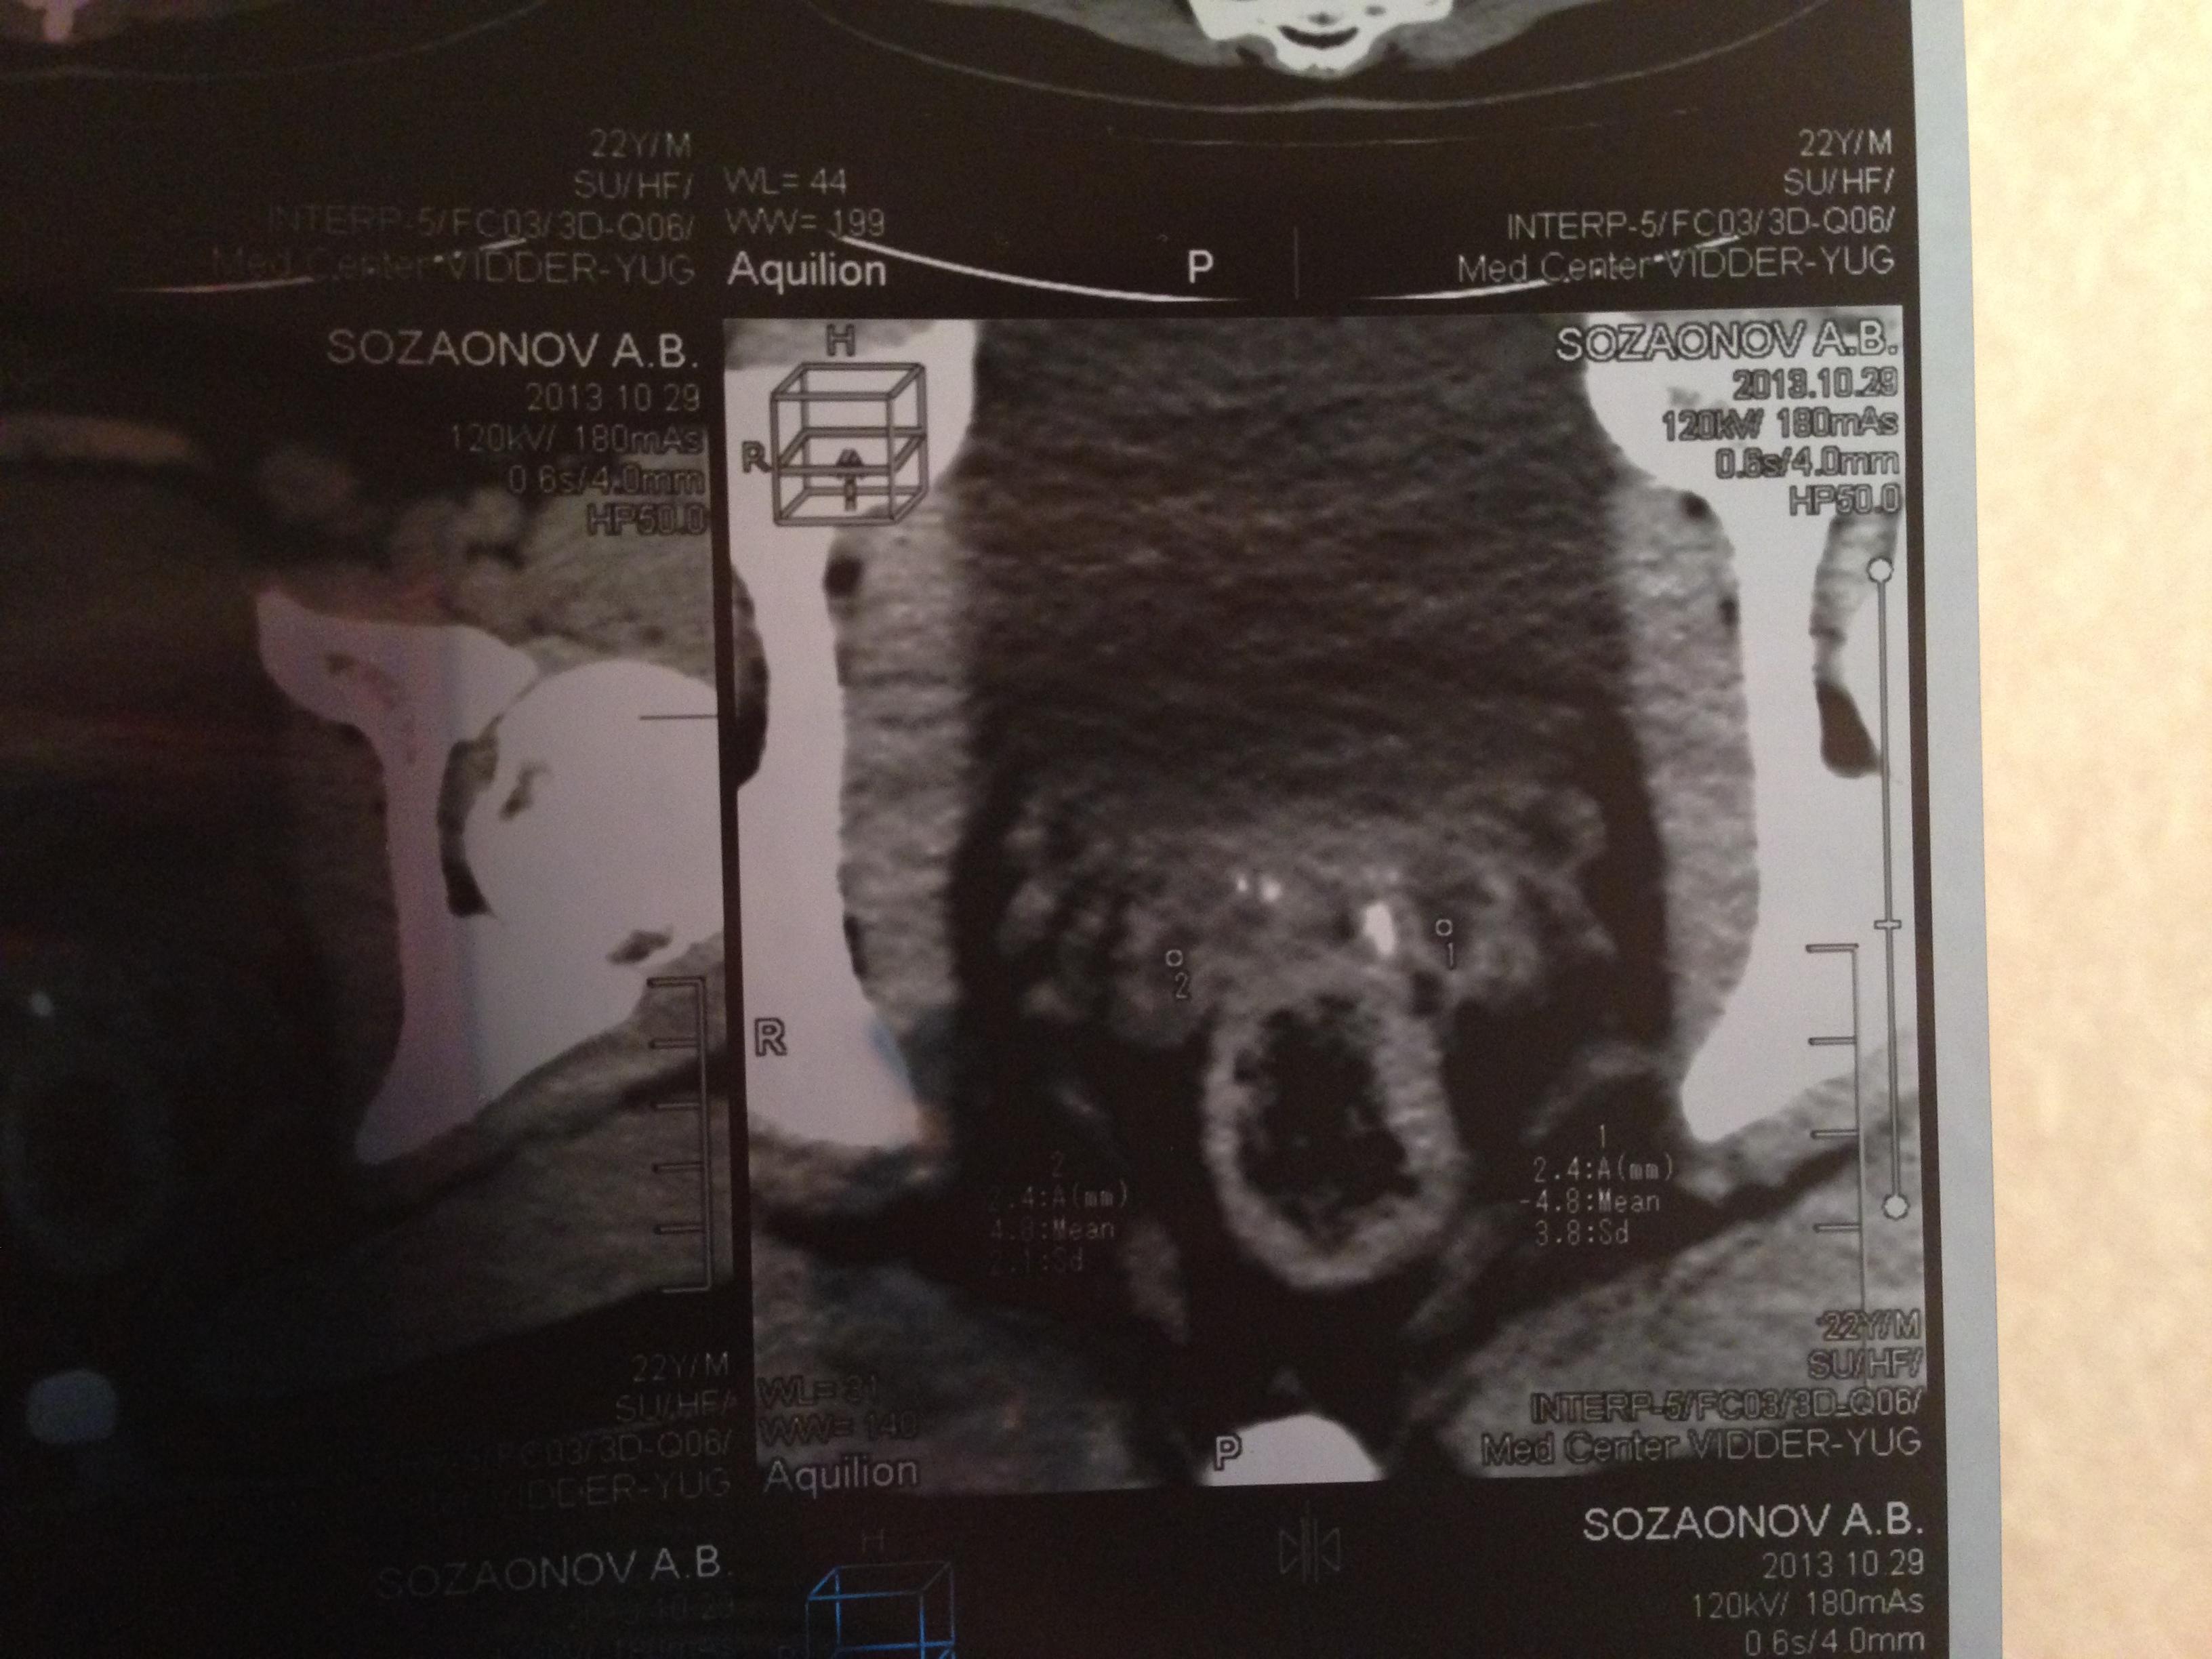

Семенные пузырьки-конфигурация не совсем типична,примерный размер правого 26*28мм.Отмечаются признаки кистовидной трансформации и микрокальцинации обоих пузырьков.Наибольшая из кист слева достигает 9 мм.Обращает на себя внимание неравномерная кальцинация стенок крупных регионарных(текстикулярных)артерий с обоих сторон.

Заключение:на момент исследования,КТ-данных за наличие внеорганных дополнительных патологических образований,лимфоденопатии или свободной жидкости в области таза не выявлено.КТ-признаки в пользу проявлений калькулезного везикулита с элементами кистовидной трансформации семенных пузырьков.